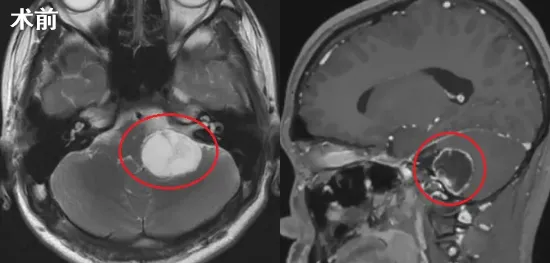

直到沫沫在另一家医院拍了核磁,真相才浮出水面:原来是在CPA区和颈静脉孔区长了一个不小的肿瘤!

尽管沫沫年仅15岁,但他早已拥有了为自己的人生负责的能力。从影像上看,这个肿瘤位于颈静脉孔区,沿舌下神经管区走行,边缘清楚,最大横断面约2.4cmx2.0cm,左侧小脑半球、脑干略受挤压。

然而,要想解除这个隐患并非易事,颈静脉孔区是侧颅底的关键结构,解剖关系复杂,被称为“神经血管交叉路口”,有重要的血管和神经通过,因此也成为手术的重难区。而沫沫的肿瘤除了位置深,其解剖结构也异常复杂,与后组颅神经、脑干、颈内动静脉等关系紧密,手术难度更大,风险也更高。